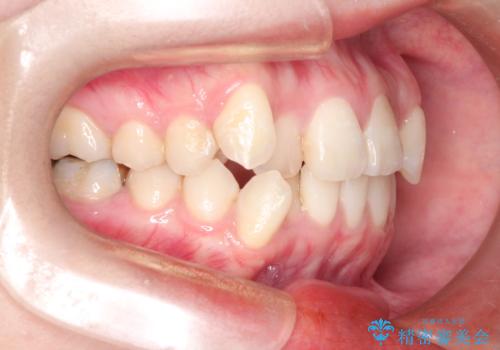

- 八重歯と前歯のガタガタを主訴に来院されました。

左下の奥歯がすでに1本抜歯されており、ブリッジを装着されていました。

ブリッジを除去して、左下以外の上顎両側と右下の歯を合計3本抜歯して矯正する計画としました。